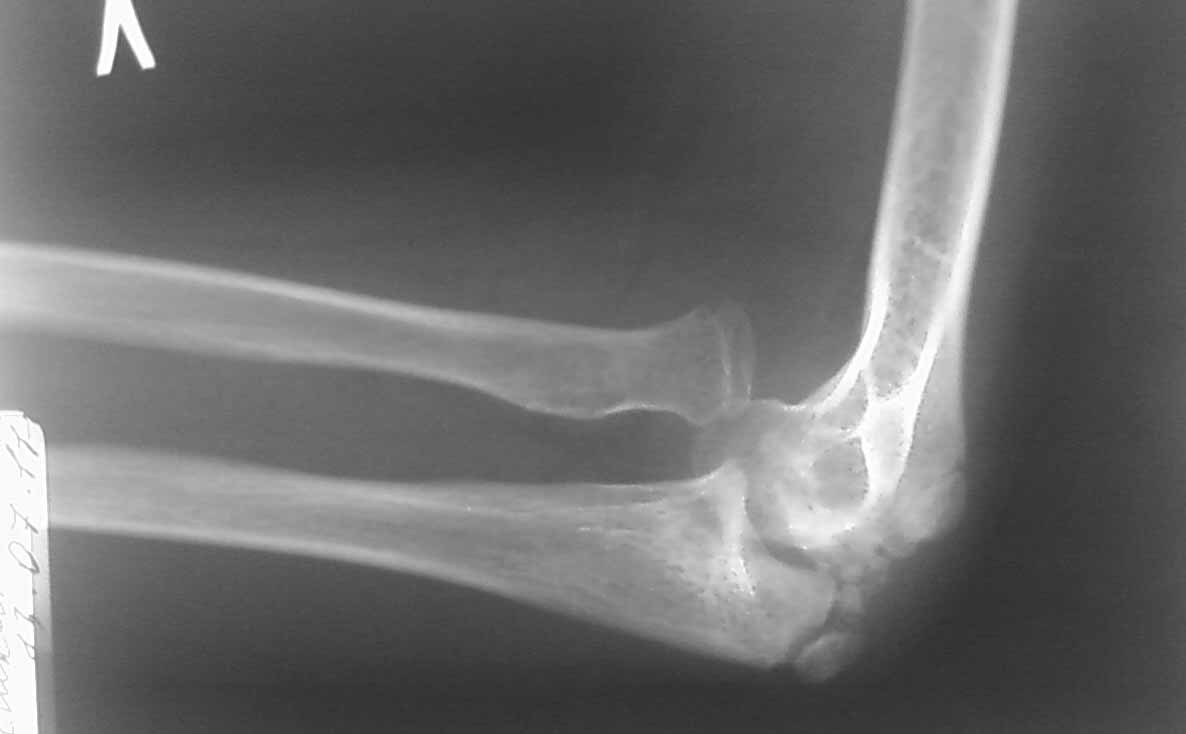

Снимок в боковой проекции не получилось сразу отправить.

Ответ собственно на все вопросы на боковой рентгенограмме: вывих лучевой кости. Либо перенесенный недиагносцированный-нелеченный Монтедж (повреждение Монтаджа: вывих лучевой кости с переломом локтевой кости). Более редкий вариант (скорее всего выявили бы раньше - врожденный вывих лучевой кости. Но честно говоря патология крайне редкая, да и не очень похоже.